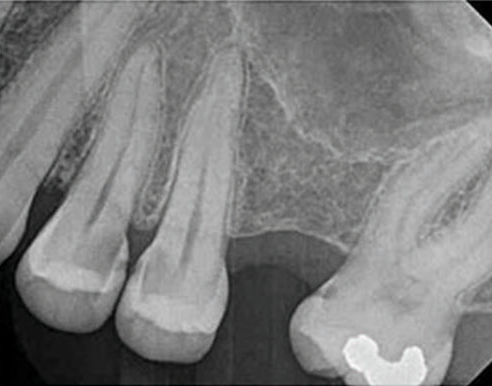

(3.) Preoperative radiograph of asymptomatic carious exposures on teeth Nos. 12 and 13.

Figure 3

(4.) Postoperative radiograph of teeth Nos. 12 and 13 following treatment with direct pulp caps using a bioceramic dentin substitute material.

Figure 4

The goal of direct pulp capping is to cover healthy or reversibly inflamed pulps that have been mechanically exposed during operative procedures or trauma.3 In direct pulp capping procedures, the chosen material is applied directly to the pulp in an effort to maintain pulp vitality and encourage the formation of directly adjacent tertiary reparative dentin (Figure 3 and Figure 4).7 Clinical studies have shown a greater rate of success when direct pulp capping is performed using MTA (85%) when compared with calcium hydroxide (52%) and similar rates of success when MTA is compared with newer calcium silicate materials.5,11 Histologic studies have shown an increase in dentin bridge formation and lower levels of pulpal inflammation adjacent to bioceramic direct pulp caps, including those placed with MTA and those placed with newer bioceramic materials.3,12